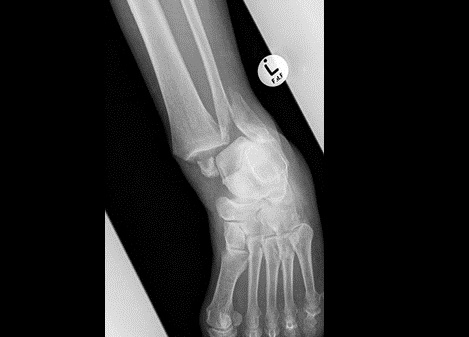

Fig5. - Fracture dislocation of the ankle joint.

Fig5. - Treated with open reduction and internal fixation with plates and screws.